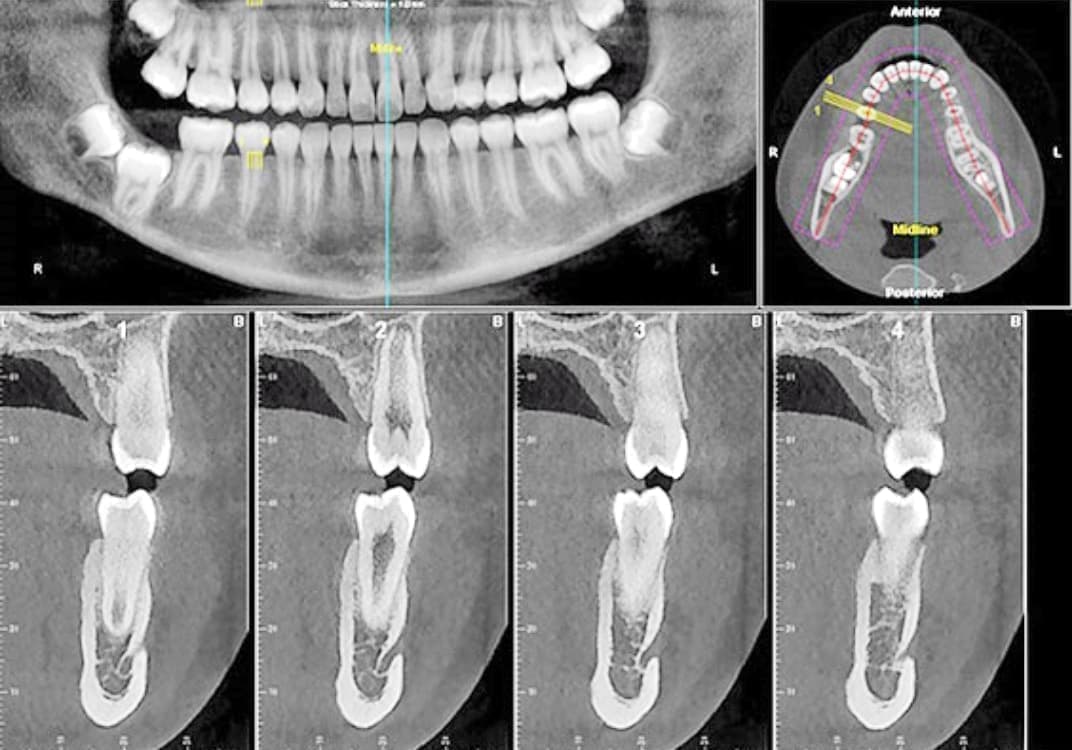

CT・3Dレントゲン

Digital CT

大学・総合病院クラスでしか撮影出来なかったCT撮影が可能!

CTといえば、大学病院や総合病院にある大きな装置を連想されると思います。

通常CT撮影は、多額の費用を払い、解析・診断等に1~2週間の時間を要します。

近年、技術の進歩と共に正確な診査を元とした高度な治療を求められるようになりました。

当院では即座にCT撮影をすることが出来、より的確な治療方針を提示できます。

歯科用CT(3D)は、コンピュータを駆使したデータ処理と画像の再構成で、断層写真を得ることができる装置です。

根管治療、親知らずの抜歯や歯周病治療、歯列矯正など様々な分野で、CTによる正確な情報を元に、的確な治療計画を立てることが出来ます。

超高感度だから被曝量が軽減!お子様にも優しいレントゲン!

デジタルレントゲンに使われているX線センサーは、デジタルならではの高感度!

照射時間が短縮され、より低線量でのレントゲン画像取得が可能となります。

また、パソコンのデジタルモニターに直接映像を映し出すことが出来るため、従来行われていたレントゲン写真の現像など、手間もなくなりました。

また環境にも優しく、スピーディーな対応が可能となります。

歯科用CTは少ない被爆で安心安全!

一般的な医療向けCTは、歯科医院で撮影するパノラマ写真の約10倍以上の放射線を照射するといわれます。

当院の歯科用CTデジタルレントゲンは、従来のフィルムを使用したレントゲン撮影に比べ、人体に受ける放射線の量を約1/4~1/10に抑える事が可能です。

照射時間がかなり短く約10秒ほどで済み、安心安全です。